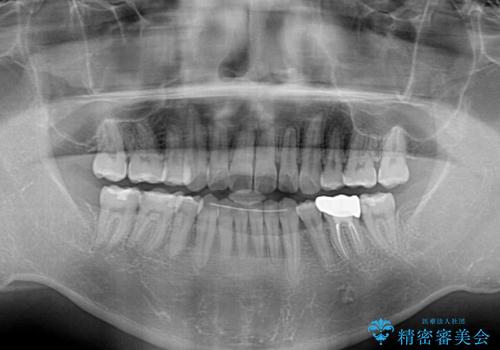

- 高校時代に行った抜歯矯正が後戻りをしたとのことで来院された患者様です。

下顎骨が左側に変位しているため、正中が合わないことは予想できましたが、歯列が整った後も咬み合わせが安定せず、咬み合わせを落ち着かせるために1年以上の期間を要しました。